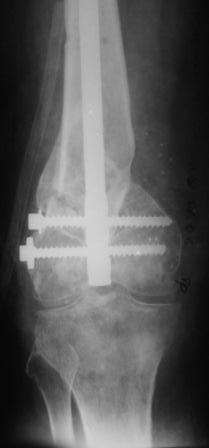

Уважаемые коллеги! Представляю на ваш суд ближйший результаты лечения.

Раннее послеоперационное течение не очень спокойное- из раны было сукровичное отделяемое, но сейчас вроде идет на поправку(на фоне интенсивного лечения). В аттаче рентгенограммы.